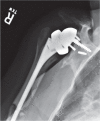

Since the introduction of reverse total shoulder arthroplasty (RTSA) in 1987 (in Europe) and 2004 (in the United States), the number of RTSAs performed annually has increased.Although the main indication for RTSA has been rotator cuff tears, indications have expanded to include several shoulder conditions, many of which involve dysfunction of the rotator cuff.RTSA complications have been reported to affect 19% to 68% of patients and include acromial fracture, haematoma, infection, instability, mechanical baseplate failure, neurological injury, periprosthetic fracture and scapular notching.Current controversies in RTSA include optimal baseplate positioning, humeral neck-shaft angle (135° versus 155°), glenosphere placement (medial, lateral or bony increased offset RTSA) and subscapularis repair.Improvements in prosthesis design, surgeon experience and clinical results will need to occur to optimize this treatment for many shoulder conditions. Cite this article: EFORT Open Rev 2018;3:58-69 DOI: 10.1302/2058-5241.3.170044.